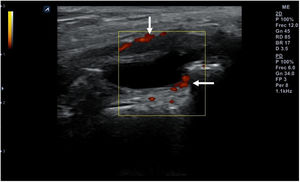

Técnica de exploraciónLa exploración ecográfica se realiza con sonda lineal de alta frecuencia (7,5-12MHz). Se debe hacer de forma estandarizada en las distintas áreas anatómicas, que permita identificar los diferentes tejidos, tanto normales como patológicos, observados en reposo y en movimiento. Los signos ecográficos patológicos habituales son la colección hipo- o anecoica comprimible y desplazable en recesos articulares en los derrames (fig. 10), el engrosamiento hipo- o anecoico del tejido en una vaina sinovial con o sin líquido en la tenosinovitis (fig. 11), la interrupción y espiculación de la línea cortical en las erosiones óseas (fig. 12), la aparición de material ecogénico en el espacio sinovial o articular en las sinovitis y el pannus respectivamente, y la presencia de señal doppler en los procesos con inflamación activa (fig. 13). Deben identificarse en 2 planos distintos para evitar la confusión por la presencia habitual de artefactos. Se ha de aplicar gel suficiente que permita el contacto de toda la superficie de la sonda con la piel, evitando el aire entre ambos, y se debe ejercer una presión firme pero no excesiva, que impida colapsar los neovasos visibles mediante el doppler. Estos serán más fáciles de encontrar con la articulación en flexoextensión fisiológica.

La ecografía permite detectar sinovitis y erosiones de forma mucho más precoz que la radiografía convencional (RX), por lo que es útil para el diagnostico y seguimiento. Su inmediatez y disponibilidad la hacen más aplicable que la RM. Además, detecta inflamación con mayor sensibilidad que la exploración física (EF) y permite distinguir entre derrame y sinovitis en escala de grises27. Con la técnica de power-doppler permite localizar neovascularización sinovial relacionada con actividad inflamatoria, siendo la sinovitis el mejor predictor de erosión radiográfica28,29.Esto la hace especialmente eficaz para el diagnóstico en fases iniciales de la artritis cuando la EF no puede aclarar aún la existencia de signos inflamatorios articulares, si bien sus hallazgos no son específicos de artritis reumatoide. También permite valorar la extensión de la artritis, mediante la exploración ampliada de las articulaciones de manos, muñecas y metatarsofalángicas, permitiendo detectar inflamación en articulaciones aún asintomáticas30,31. Hay datos sólidos que demuestran la capacidad de la ecografía para la detección más precoz de erosiones que la RX32,33, aunque su capacidad es inferior a la de la RM33–35.

Varios estudios han demostrado la rentabilidad de la RM y la ecografía en la identificación de la sinovitis, de forma mucho más sensible que la EF27. Además, ambas técnicas permiten la valoración periarticular, pudiendo identificar entesitis, que reduce la probabilidad de artritis reumatoide y orienta hacia una espondiloartropatía. A diferencia de la RX, no solo aportan una imagen del daño estructural residual sino que muestran en tiempo real el grado de sinovitis, permitiendo detectar no solo la progresión de la enfermedad debida a la inflamación pasada, sino también medir la actividad actual de la enfermedad, información que está mucho más cercana a la toma de decisiones cotidianas.